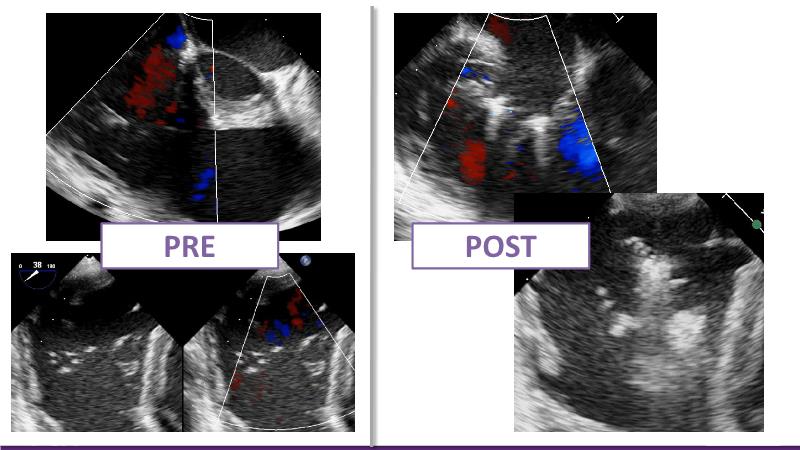

Based on an in-depth review of the data from TRILUMINATE pivotal, a randomized trial whose findings were recently published in the NEW ENGLAND JOURNAL of MEDICINE, this lecture explains how these results will impact clinical practice in the treatment of tricuspid regurgitation. Join the speakers and learn more.

- To understand why it is key to intervene in tricuspid regurgitation disease - A safe option for an unmet need

- To learn how TRILUMINATE Pivotal - the first randomised trial - is impacting the clinical practice in tricuspid regurgitation treatment

- To understand how the broadest body of evidence supports TriClip therapy as first line treatment option for tricuspid regurgitation